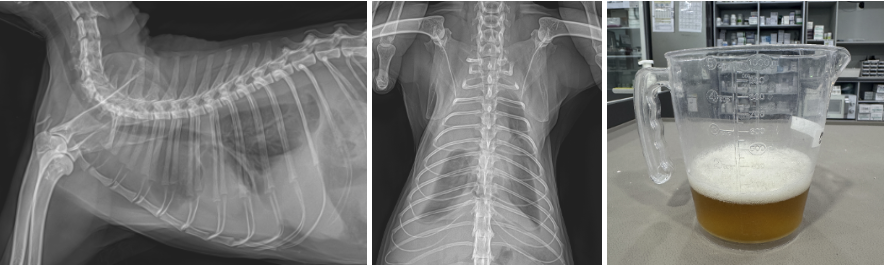

1️⃣ X-Ray 검진

내원 시 청진에서 폐음이 약하게 들렸고, 방사선 촬영 결과 양측 흉강에 다량의 액체 음영(흉수)이 확인되었습니다.

내원 당시 방사선상 확인되는 다량의 고양이 흉수 (1번, 2번 사진) 응급 흉수천자 후 제거된 다량의 흉수 (3번 사진) / 출처: 에스동물메디컬센터

즉시 응급 흉수천자를 통해 다량의 흉수를 배액하였고 호흡 안정화 이후 흉수의 원인 파악을 위해 추가적인 검사가 진행되었습니다.